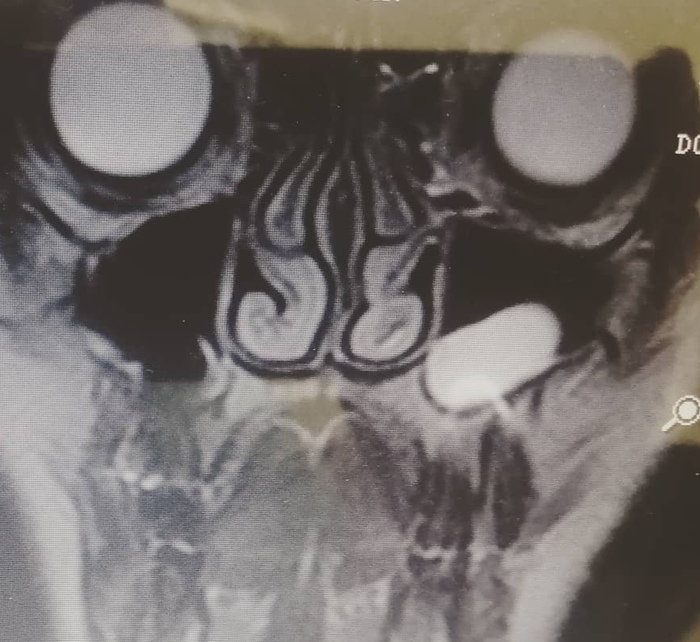

По итогу, при оптимальном введение, удалось понизить вирусную нагрузку в десять тысяч раз. У 5 из 6 животных поверхностный антиген HBsAg больше не определялся:

Логарифмический уровень производства антигена HBsAg

Подобный результат означает, что вирус более не активен.